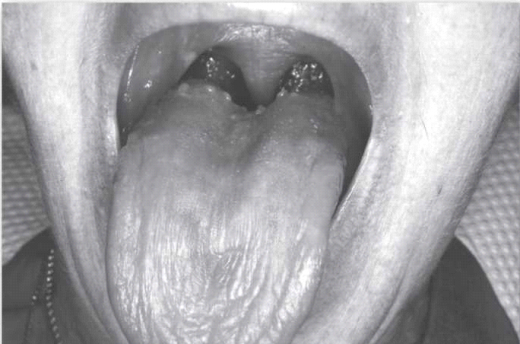

כאשר יש ירידה בהפרשת הרוק, פעולות שגרתיות כגון אכילה, בליעה או דיבור הופכות להיות קשות יותר ויותר. מצב של מחסור ברוק גורם גם לפגיעה בחוש הטעם, להופעה של פצעים בפה ולתחושה של צריבה בפה (תחושה של צריבה ו"שריפה" אופיינית לזיהום פטרייתי). ניתן לראות עששת אופיינית בשורשי השיניים וקושי בהרכבה ובהצמדה של תותבות.[2], [3], [4] במצב מתקדם ייאלצו הסובלים ממחסור ברוק לשאת עמם בכל עת בקבוק מים כדי ל"הרטיב" את הפה ולאפשר אכילה ובליעה. בשל היובש בפה, קשה מאוד להירדם ולישון. קושי זה יכול לגרום להסתגרות ולבידוד חברתי, ואף להוביל לדיכאון.

סיבה שכיחה נוספת ליובש פה היא הקרנות באזור ראש-צוואר לטיפול בסרטן הפוגעות בבלוטות הרוק. מחלות הפוגעות במערכת החיסונית, יכולות אף הן לגרום ליובש בפה. המחלה השכיחה ביותר הגורמת נזק לבלוטות הרוק היא תסמונת שיוגרן (Sjögren's syndrome),[1] שהיא מחלה אוטואימונית (Autoimmune) הגורמת הן ליובש פה והן ליובש בעיניים. מחלות נוספות הגורמות ליובש פה הן אלצהיימר (Alzheimer's), הפטיטיס C (Hepatitis C, דלקת נגיפית של הכבד מסוג C) ו-HIV (Human Immunodeficiency Virus, נגיף הכשל החיסוני).